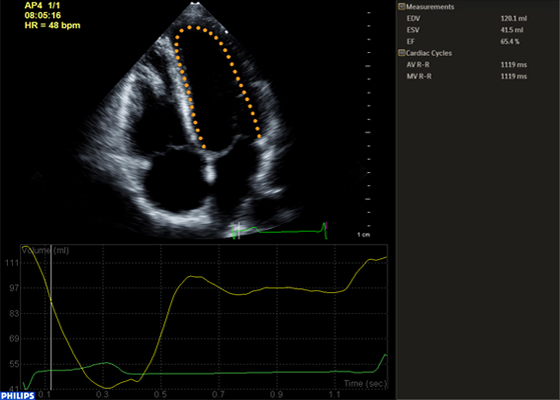

HeartModelᴬ⋅ᴵ⋅— это новое приложение для УЗИ с технологией интеллектуального анализа анатомии (AIUS), предлагающее передовые средства количественной оценки трехмерных данных в реальном времени, автоматизированное создание двумерных проекций и уверенное получение воспроизводимых результатов в эхокардиографии. Приложение HeartModelᴬ⋅ᴵ⋅ автоматически определяет, сегментирует и количественно оценивает левое предсердие (ЛП) и левый желудочек (ЛЖ) в трехмерных объемных данных.

Согласно результатам сравнительного исследования двумерного количественного анализа и анализа в режиме Live 3D HeartModelᴬ⋅ᴵ⋅ приложение HeartModelᴬ⋅ᴵ⋅ позволило сэкономить 82% времени при работе в полностью автоматическом режиме и 71% времени при минимальном ручном редактировании.

Благодаря повышенной воспроизводимости и выполнению меньшего количества этапов за меньший промежуток времени, чем требуется для традиционных методов, больше пользователей смогут увереннее проводить диагностику.